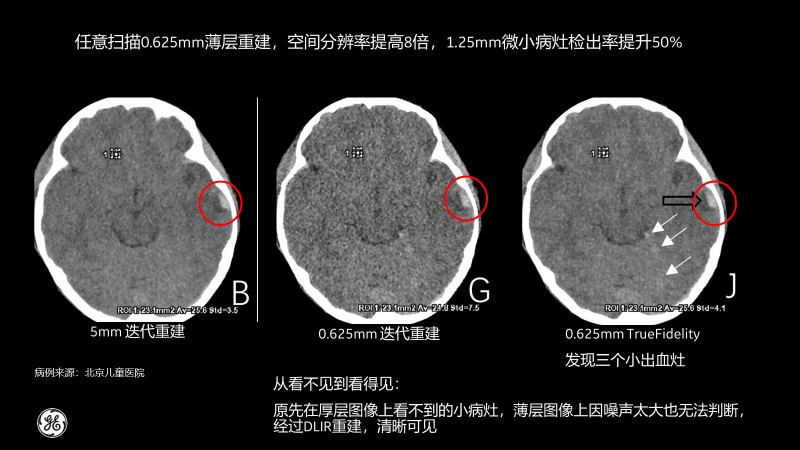

北京兒童醫院的測試病例也顯示,經過TrueFidelity,任意掃描0.625mm薄層重建,空間分辨率能提高8倍,1.25mm微小病灶檢出率提升50%,最終額外發現了3個之前看不到的微小病灶。

相比傳統CT圖像對腹部檢查一般都選擇5mm厚層重建,TrueFidelity可對任意體型任意部位的檢查進行0.625mm的薄層圖像重建,真實還原圖像的解剖細節和紋理,提高微小病灶的發現幾率,有助于早診早治,極大提高醫生的診斷信心。

尤其是對于天然對比度低的組織結構,比如腹部成像,TrueFidelity的診斷優勢尤為明顯,并為臨床診斷帶來了顯著突破。